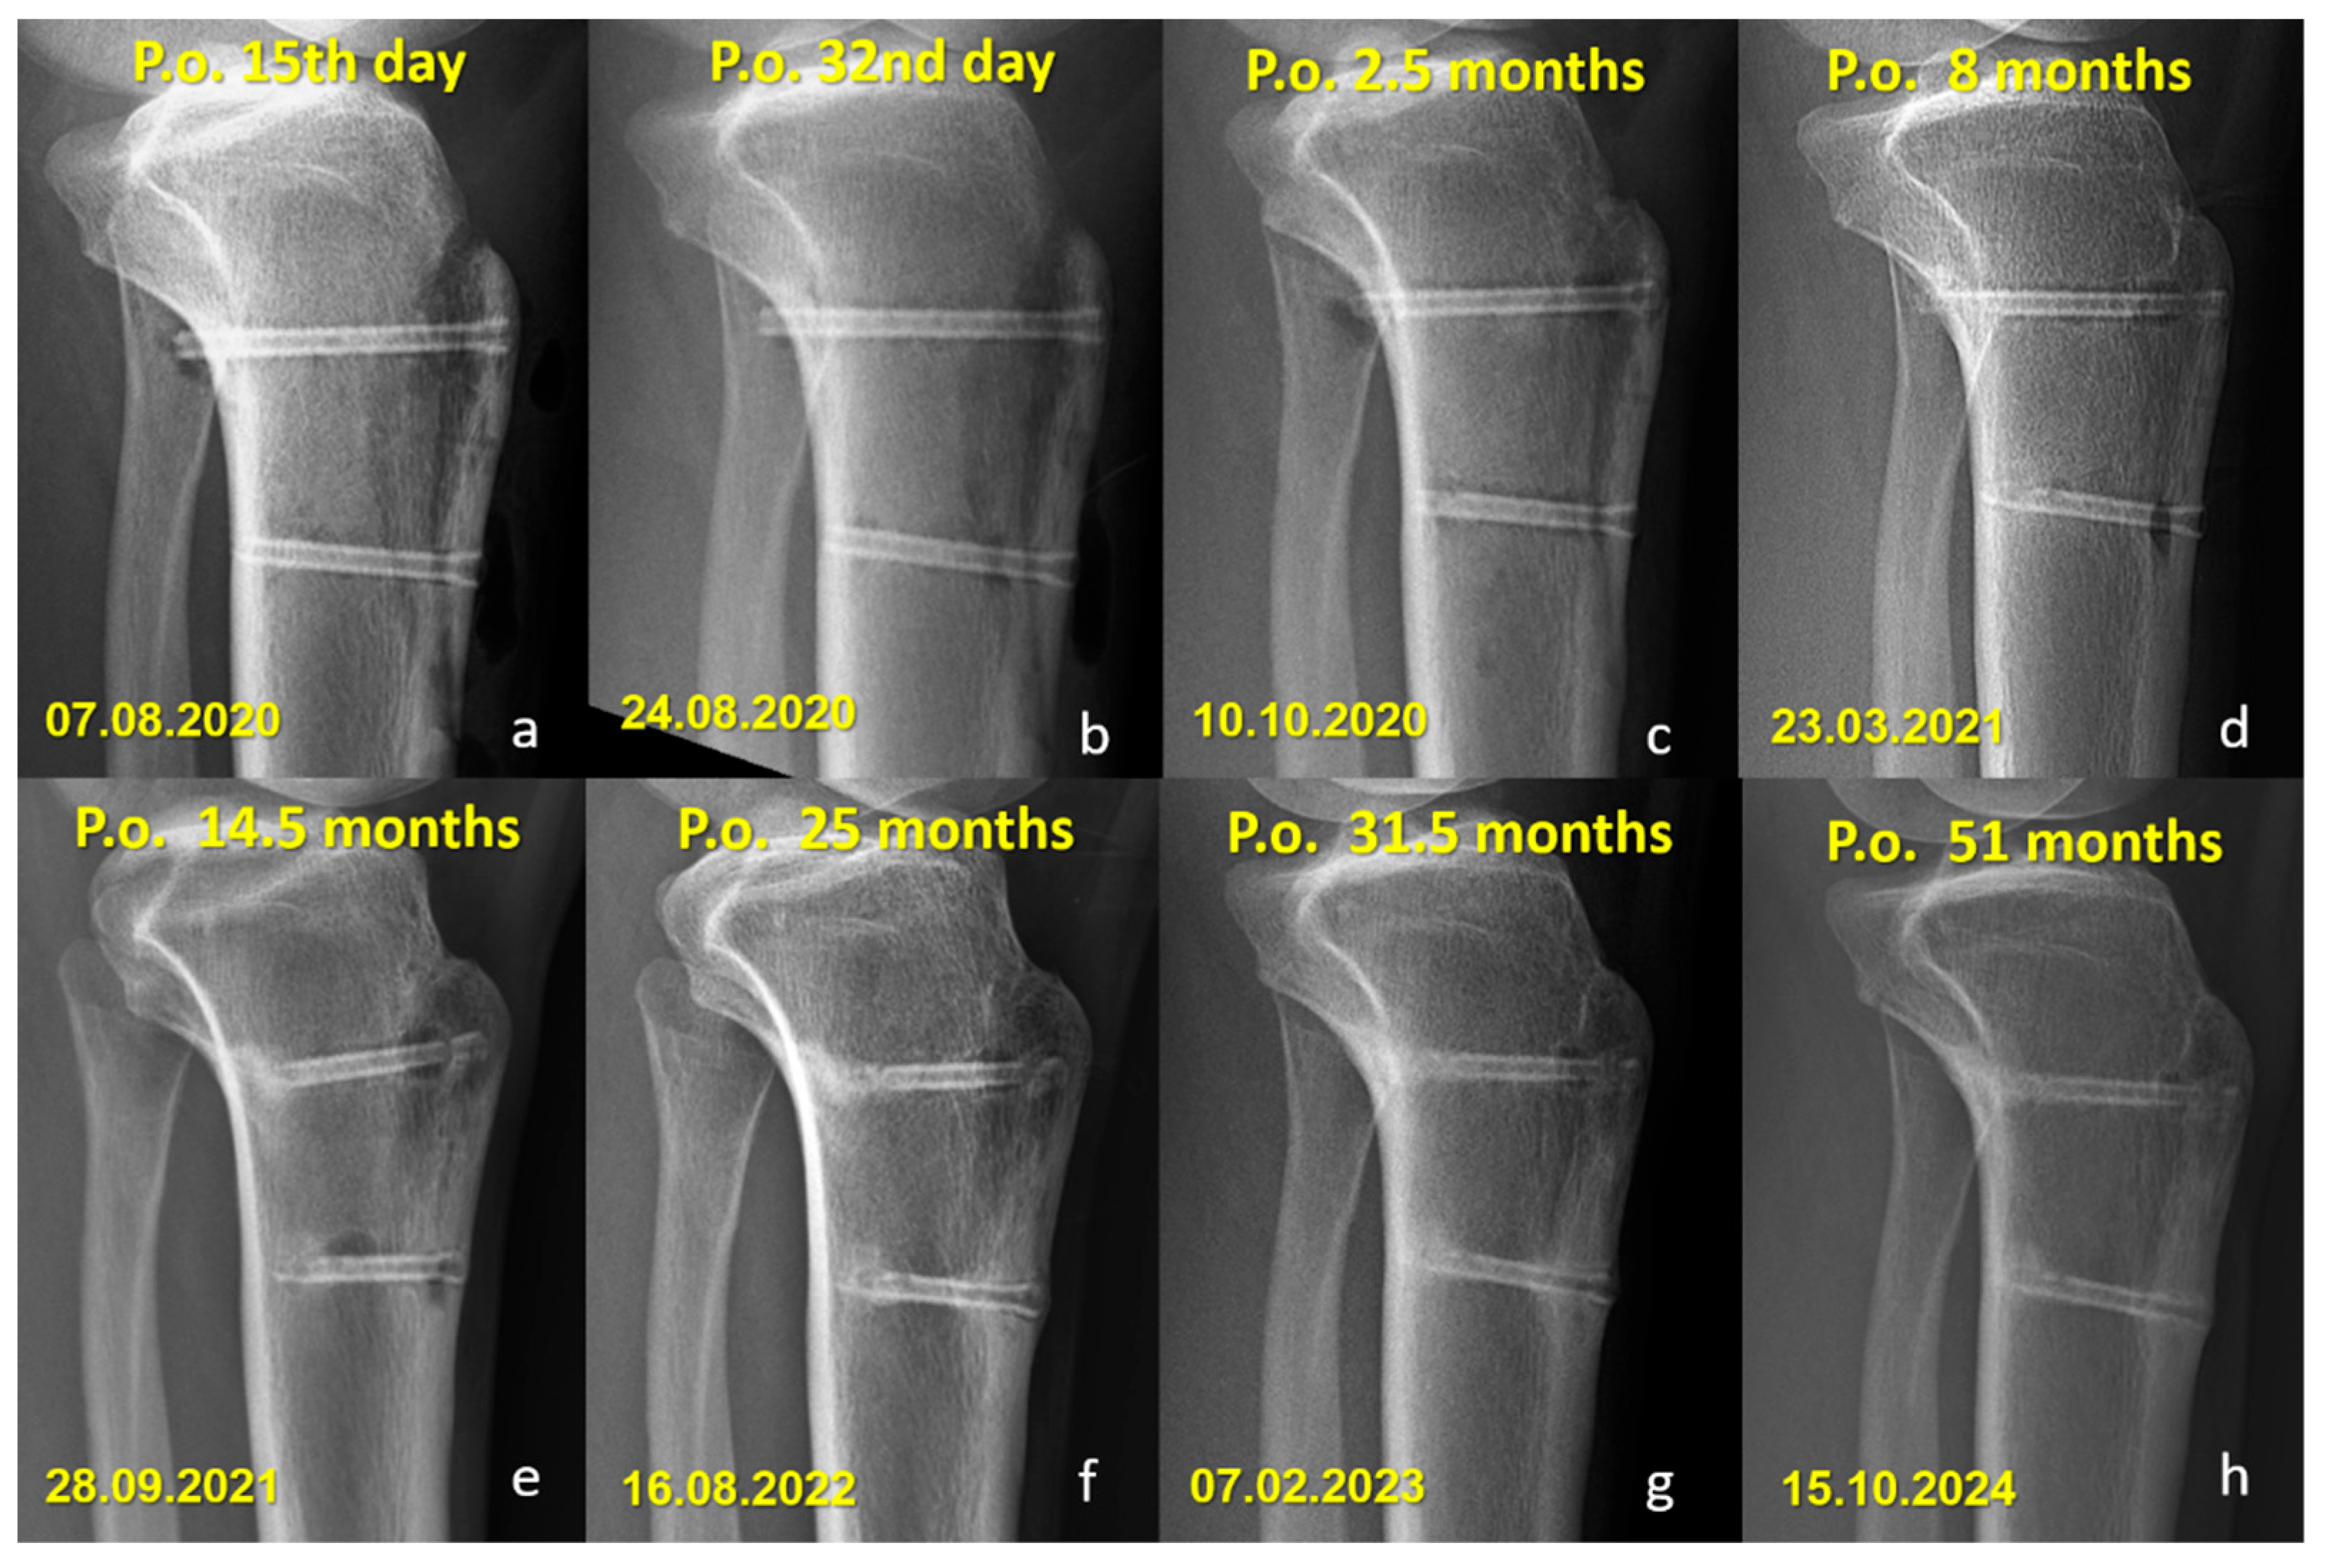

Radiographic Findings in the Mg Screw Group